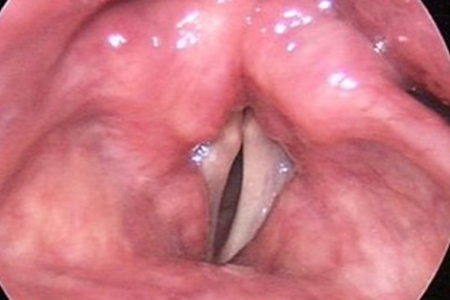

그림1. 좌측 그림에서는 성대가 양측 모두 내전이 되어 성대 폐쇄가 되지만 우측 그림에서는 성대 마비로 인한 성문부폐쇄 부전이 관찰됨.